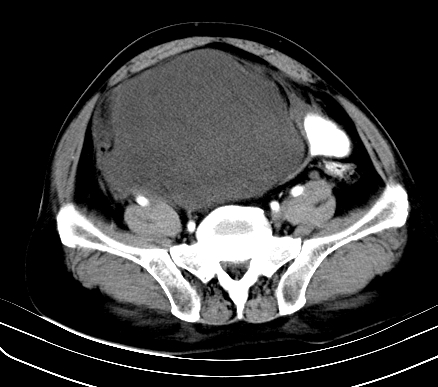

标题: CT19729B:男,74岁,因腿疼就诊,查体触腹部肿物,

增强扫描

静脉期

【ct表现】

1、肿块巨大,往往位于腹膜后,长大后才引起症状而就诊;那么位于腹膜后的肿瘤80%为恶性肿瘤。

2、实性肿瘤,增强扫描轻度不均强化,实性肿瘤一般不是好东西。

3、肿瘤边缘似见少许脂肪样密度。

4、腹膜后未见肿大淋巴结,但肿瘤于临近的肠管及组织接触紧密。

【诊断】

腹部占位,考虑位于腹膜后的恶性肿瘤,脂肪肉瘤(实体型)可能性大。

病变基本位于下腹部正中,膀胱有联系。完全是囊性。首先考虑脐输尿管囊肿。

应该是腹腔病变,病灶较大,内可见脂肪密度影,边界较清,有钻孔样改变,表皮强化,考虑畸胎瘤(皮样囊肿)可能性大.

术后病理结果:腹膜后脂肪肉瘤。